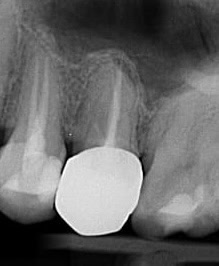

Caz 2 – Molar inferior cu șase canale

Un molar unu inferior care părea radiologic standard s-a dovedit, sub microscop, a avea șase canale, un caz extrem de rar. Fără magnificare, aceste canale nu ar fi putut fi detectate, ceea ce ar fi dus la recidivă cu probabilitate foarte mare.